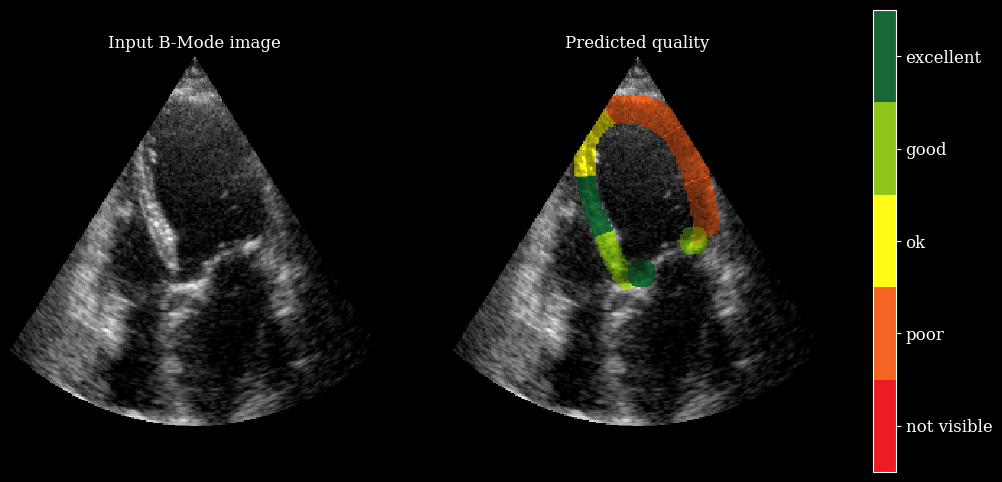

We need the arqee package for a complete visualization. The colored overlay shows the predicted regional image quality for each myocardial region.

[8]:

import arqee

frames = []

for image, mask, labels in zip(batch_np, masks, scores):

labels = [int(i) for i in labels]

image = np.squeeze(image, axis=-1)

fig, *_ = arqee.plot_quality_prediction_result(image, mask, labels)

frames.append(matplotlib_figure_to_numpy(fig))

plt.close(fig)

save_video(frames, "./myocardial_image_quality.gif", fps=10)

zea: Succesfully saved GIF to -> ./myocardial_image_quality.gif

myocardial image quality